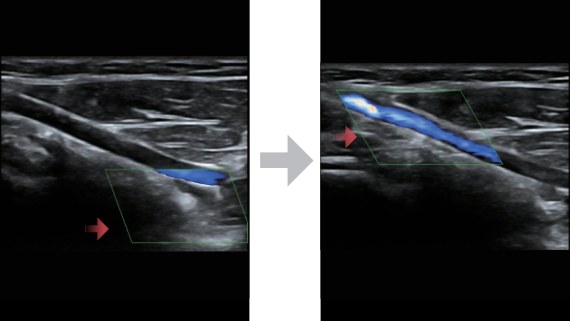

?ok y?nlĂŒ bir partner olarak, X-Insight'l? DC-60 Exp, her y?nĂŒyle gĂŒnlĂŒk klinik uygulamay? kolayl?kla ve belirsizlik olmadan y?netmenize yard?mc? olacak kapsaml? bir ??zĂŒm sunar.

MĂŒ?teri gereksinimlerine y?nelik g?rĂŒ?ler temelinde, X-Insight'l? DC-60 Exp, eXpress Clarity, eXceptional Intelligence ve eXceeding Experience ile gĂŒ?lendirilerek, hassas g?rĂŒntĂŒlemeyle yĂŒksek verimlilik sa?layacak ?ekilde tasarlanm??t?r.